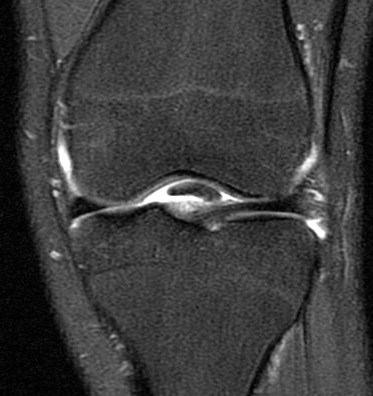

15 y/o F soccer injury lateral pain. r/o lateral meniscus.

Figure 1 for case Unstable displaced lateral meniscus flap tear( RID2763 )

Figure 1

Unstable displaced lateral meniscus flap tear( RID2763 )